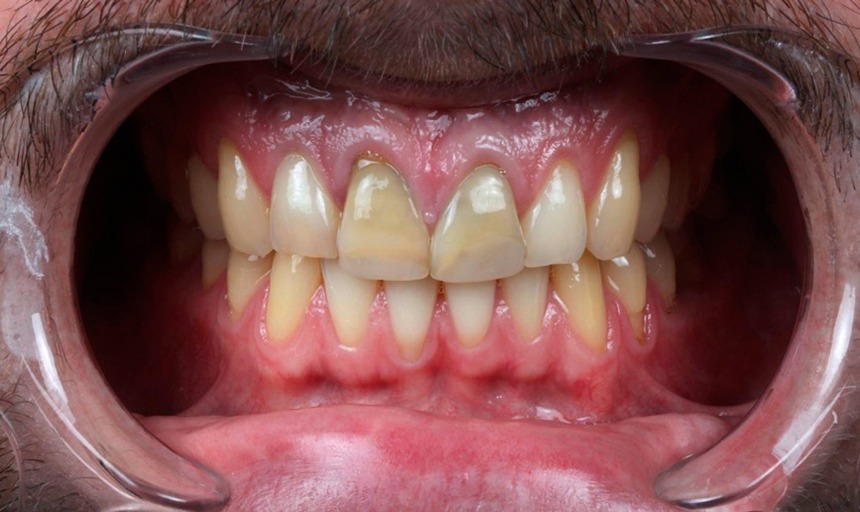

Ortodoncia

BeforeAfter